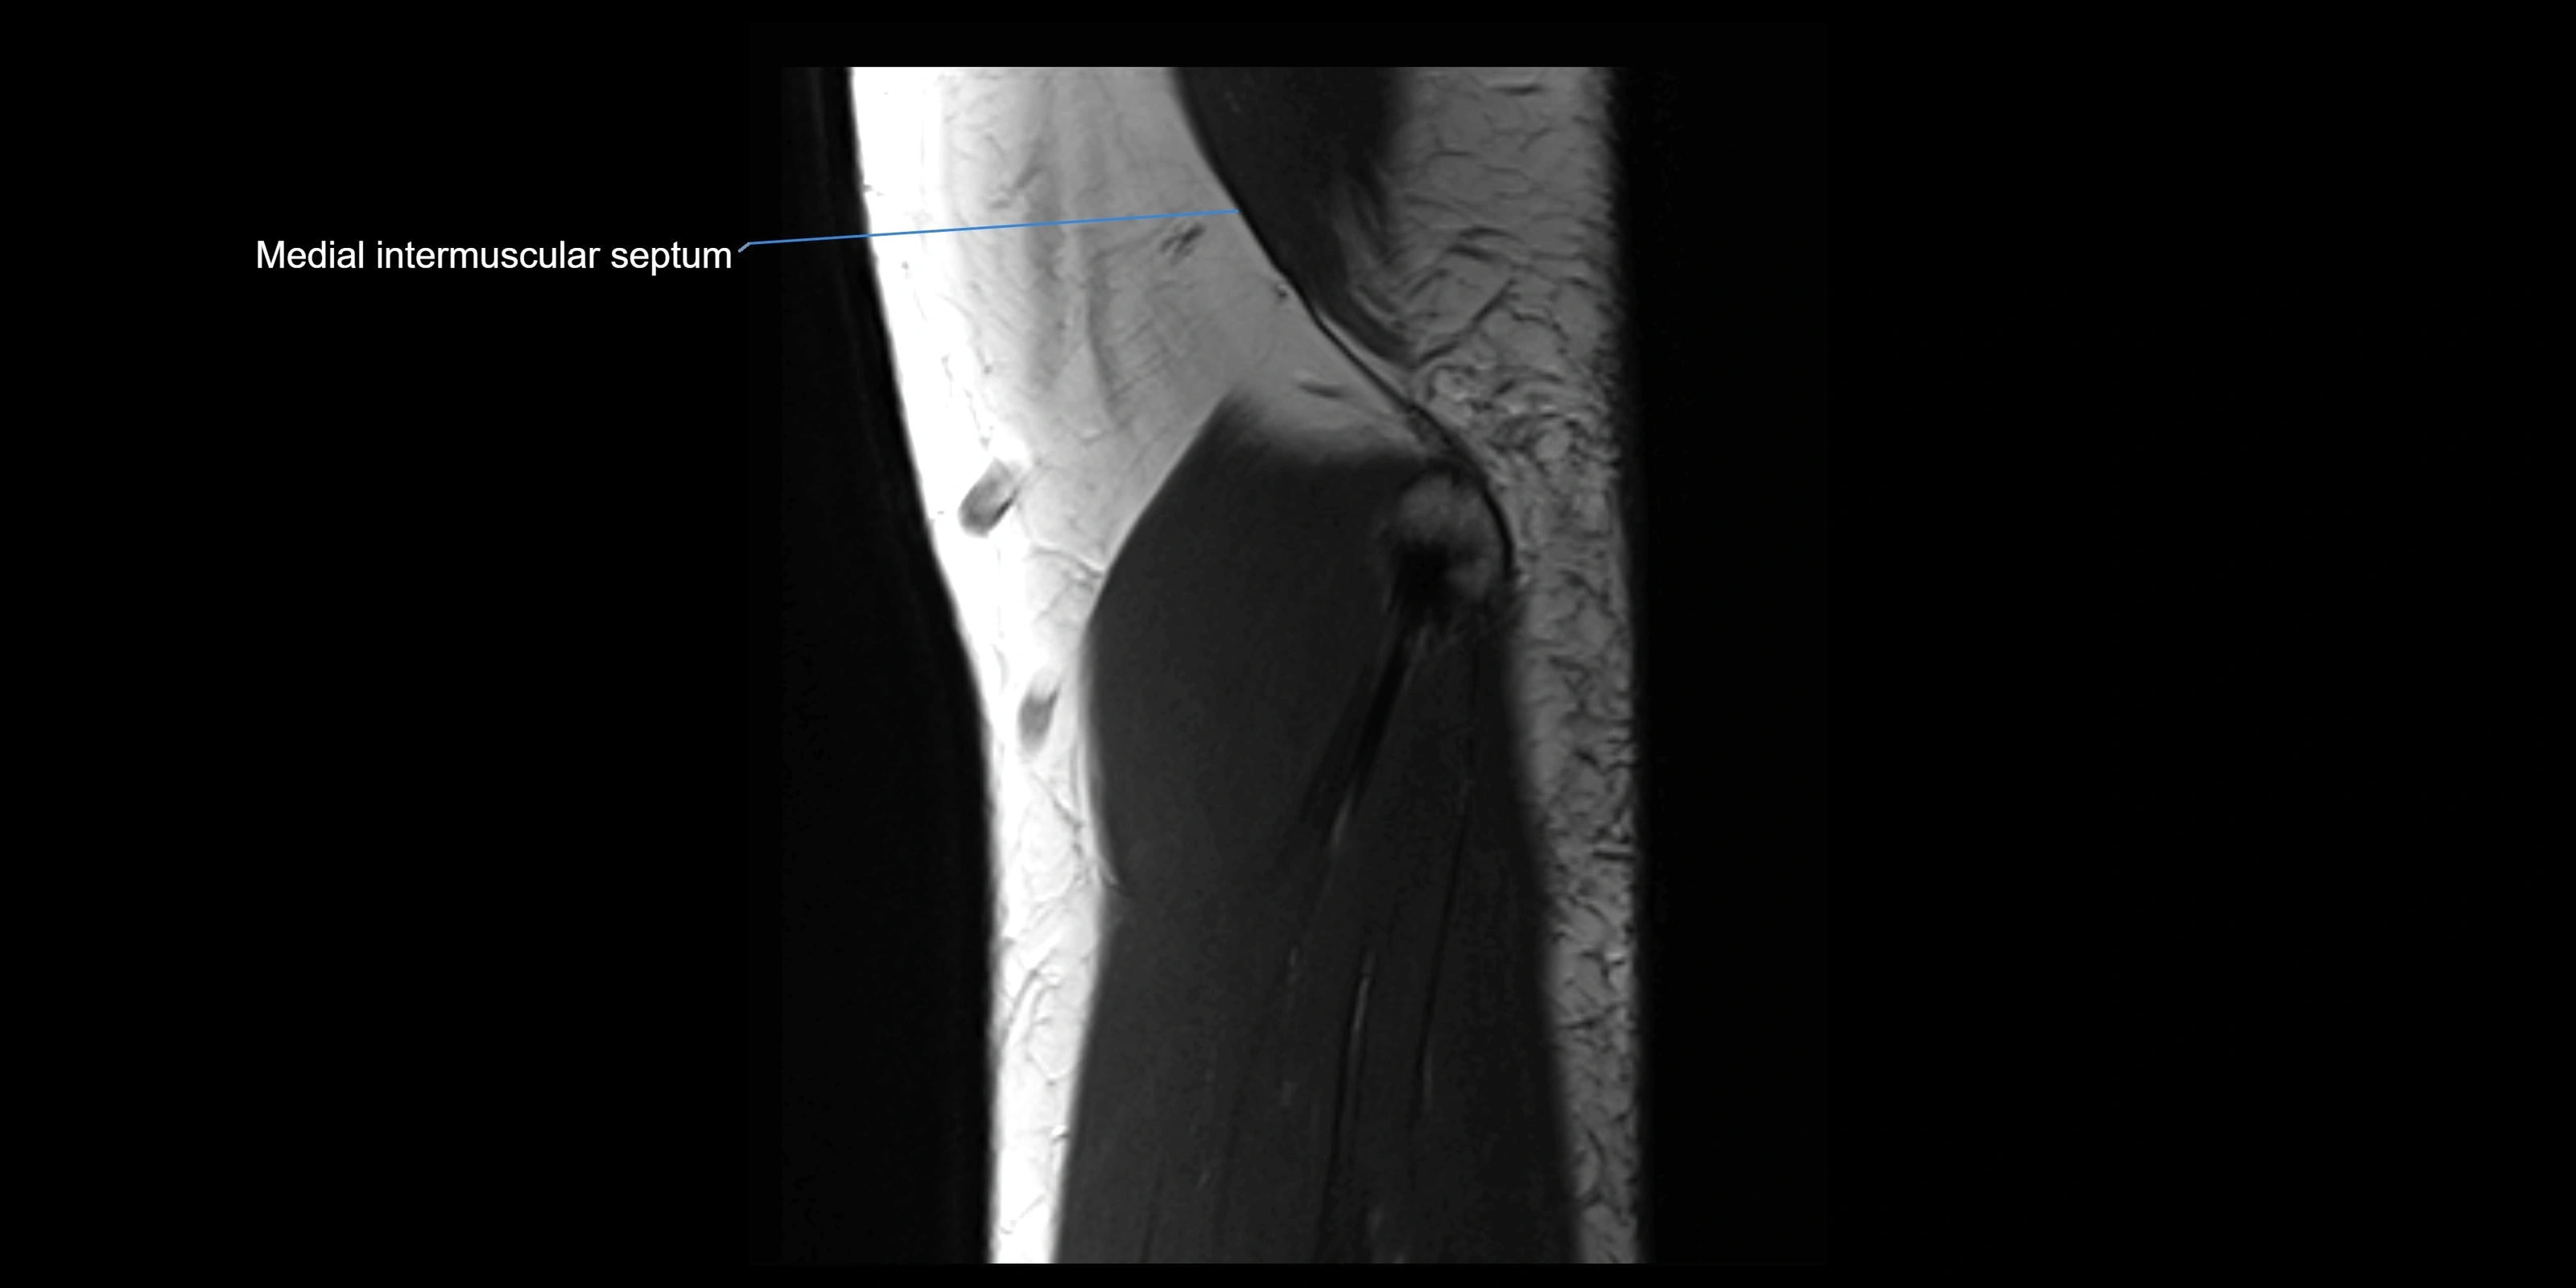

image